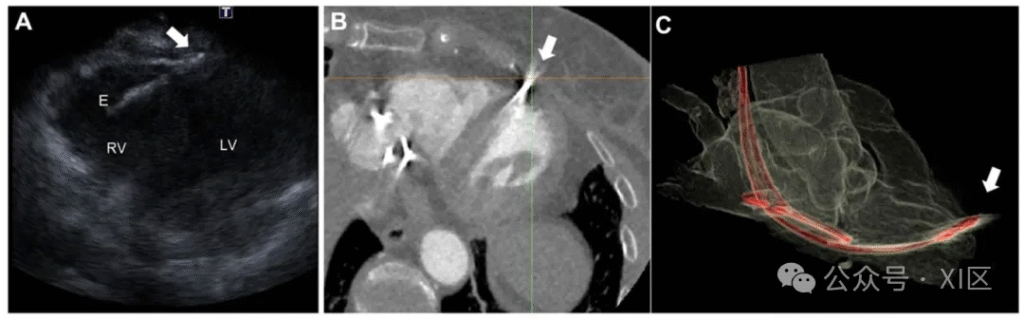

心脏计算机断层扫描(CCT)在心脏植入式电子器械(CIED)评估中的应用。一名 63 岁女性患者,10 年前因病态窦房结综合征植入双腔起搏器,1 年前因气胸接受起搏器翻修术,此次因膈肌及胸壁肌肉刺激症状就诊。临床检查与心电图未见明显异常;经胸超声心动图显示左右心室收缩功能正常,但提示右心室心肌可能存在穿孔(A 图)。CCT 进一步证实右心室起搏器电极位于心肌外(B 图、C 图),同时显示起搏器导线及胸壁骨骼结构,并发现心包存在少量积液。最终患者接受右心室电极拔除术并植入新起搏器 。